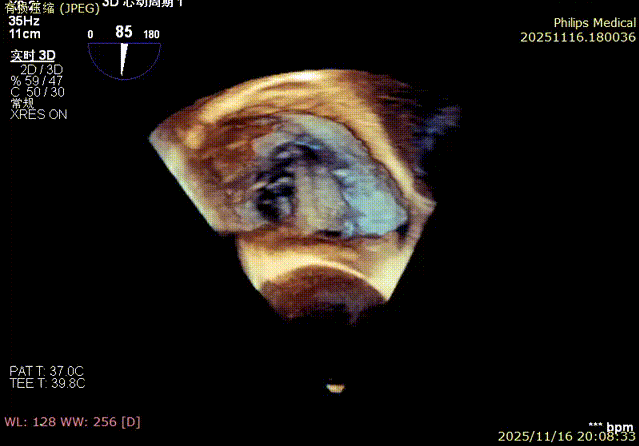

Echocardiographic Assessment: Echocardiography revealed left atrial enlargement. The left atrial appendage (LAA) orifice was 32mm with no thrombus inside. Tricuspid regurgitation was extreme (average vena contracta 18mm). Regurgitant jets were located at the anterior-septal, central, and posterior-septal commissures, with a central gap measuring approximately 13x5.9mm. The annulus was mildly dilated (average diameter 43mm). The tricuspid leaflets showed thickening and degenerative changes.

3.Steering and rotating the delivery system to target the site while engaging the anchor screw via the 3D MPR plane.

Annular area reduction: 50%

preoperative

postoperative

- Annulus Area Reduction: Decreased by 50%.